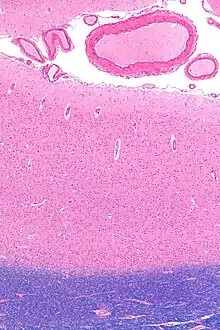

Tissue slice from the brain of an adult macaque monkey. The cerebral cortex is depicted in dark violet.